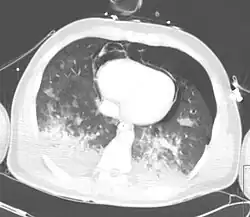

Computed tomography

Computed tomography (CT scanning) is a more sensitive test for pulmonary contusion,[8][38] and it can identify abdominal, chest, or other injuries that accompany the contusion.[43] In one study, chest X-ray detected pulmonary contusions in 16.3% of people with serious blunt trauma, while CT detected them in 31.2% of the same people.[50] Unlike X-ray, CT scanning can detect the contusion almost immediately after the injury.[48] However, in both X-ray and CT a contusion may become more visible over the first 24–48 hours after trauma as bleeding and edema into lung tissues progress.[51] CT scanning also helps determine the size of a contusion, which is useful in determining whether a patient needs mechanical ventilation; a larger volume of contused lung on CT scan is associated with an increased likelihood that ventilation will be needed.[48] CT scans also help differentiate between contusion and pulmonary hematoma, which may be difficult to tell apart otherwise.[52] However, pulmonary contusions that are visible on CT but not chest X-ray are usually not severe enough to affect outcome or treatment.[42]